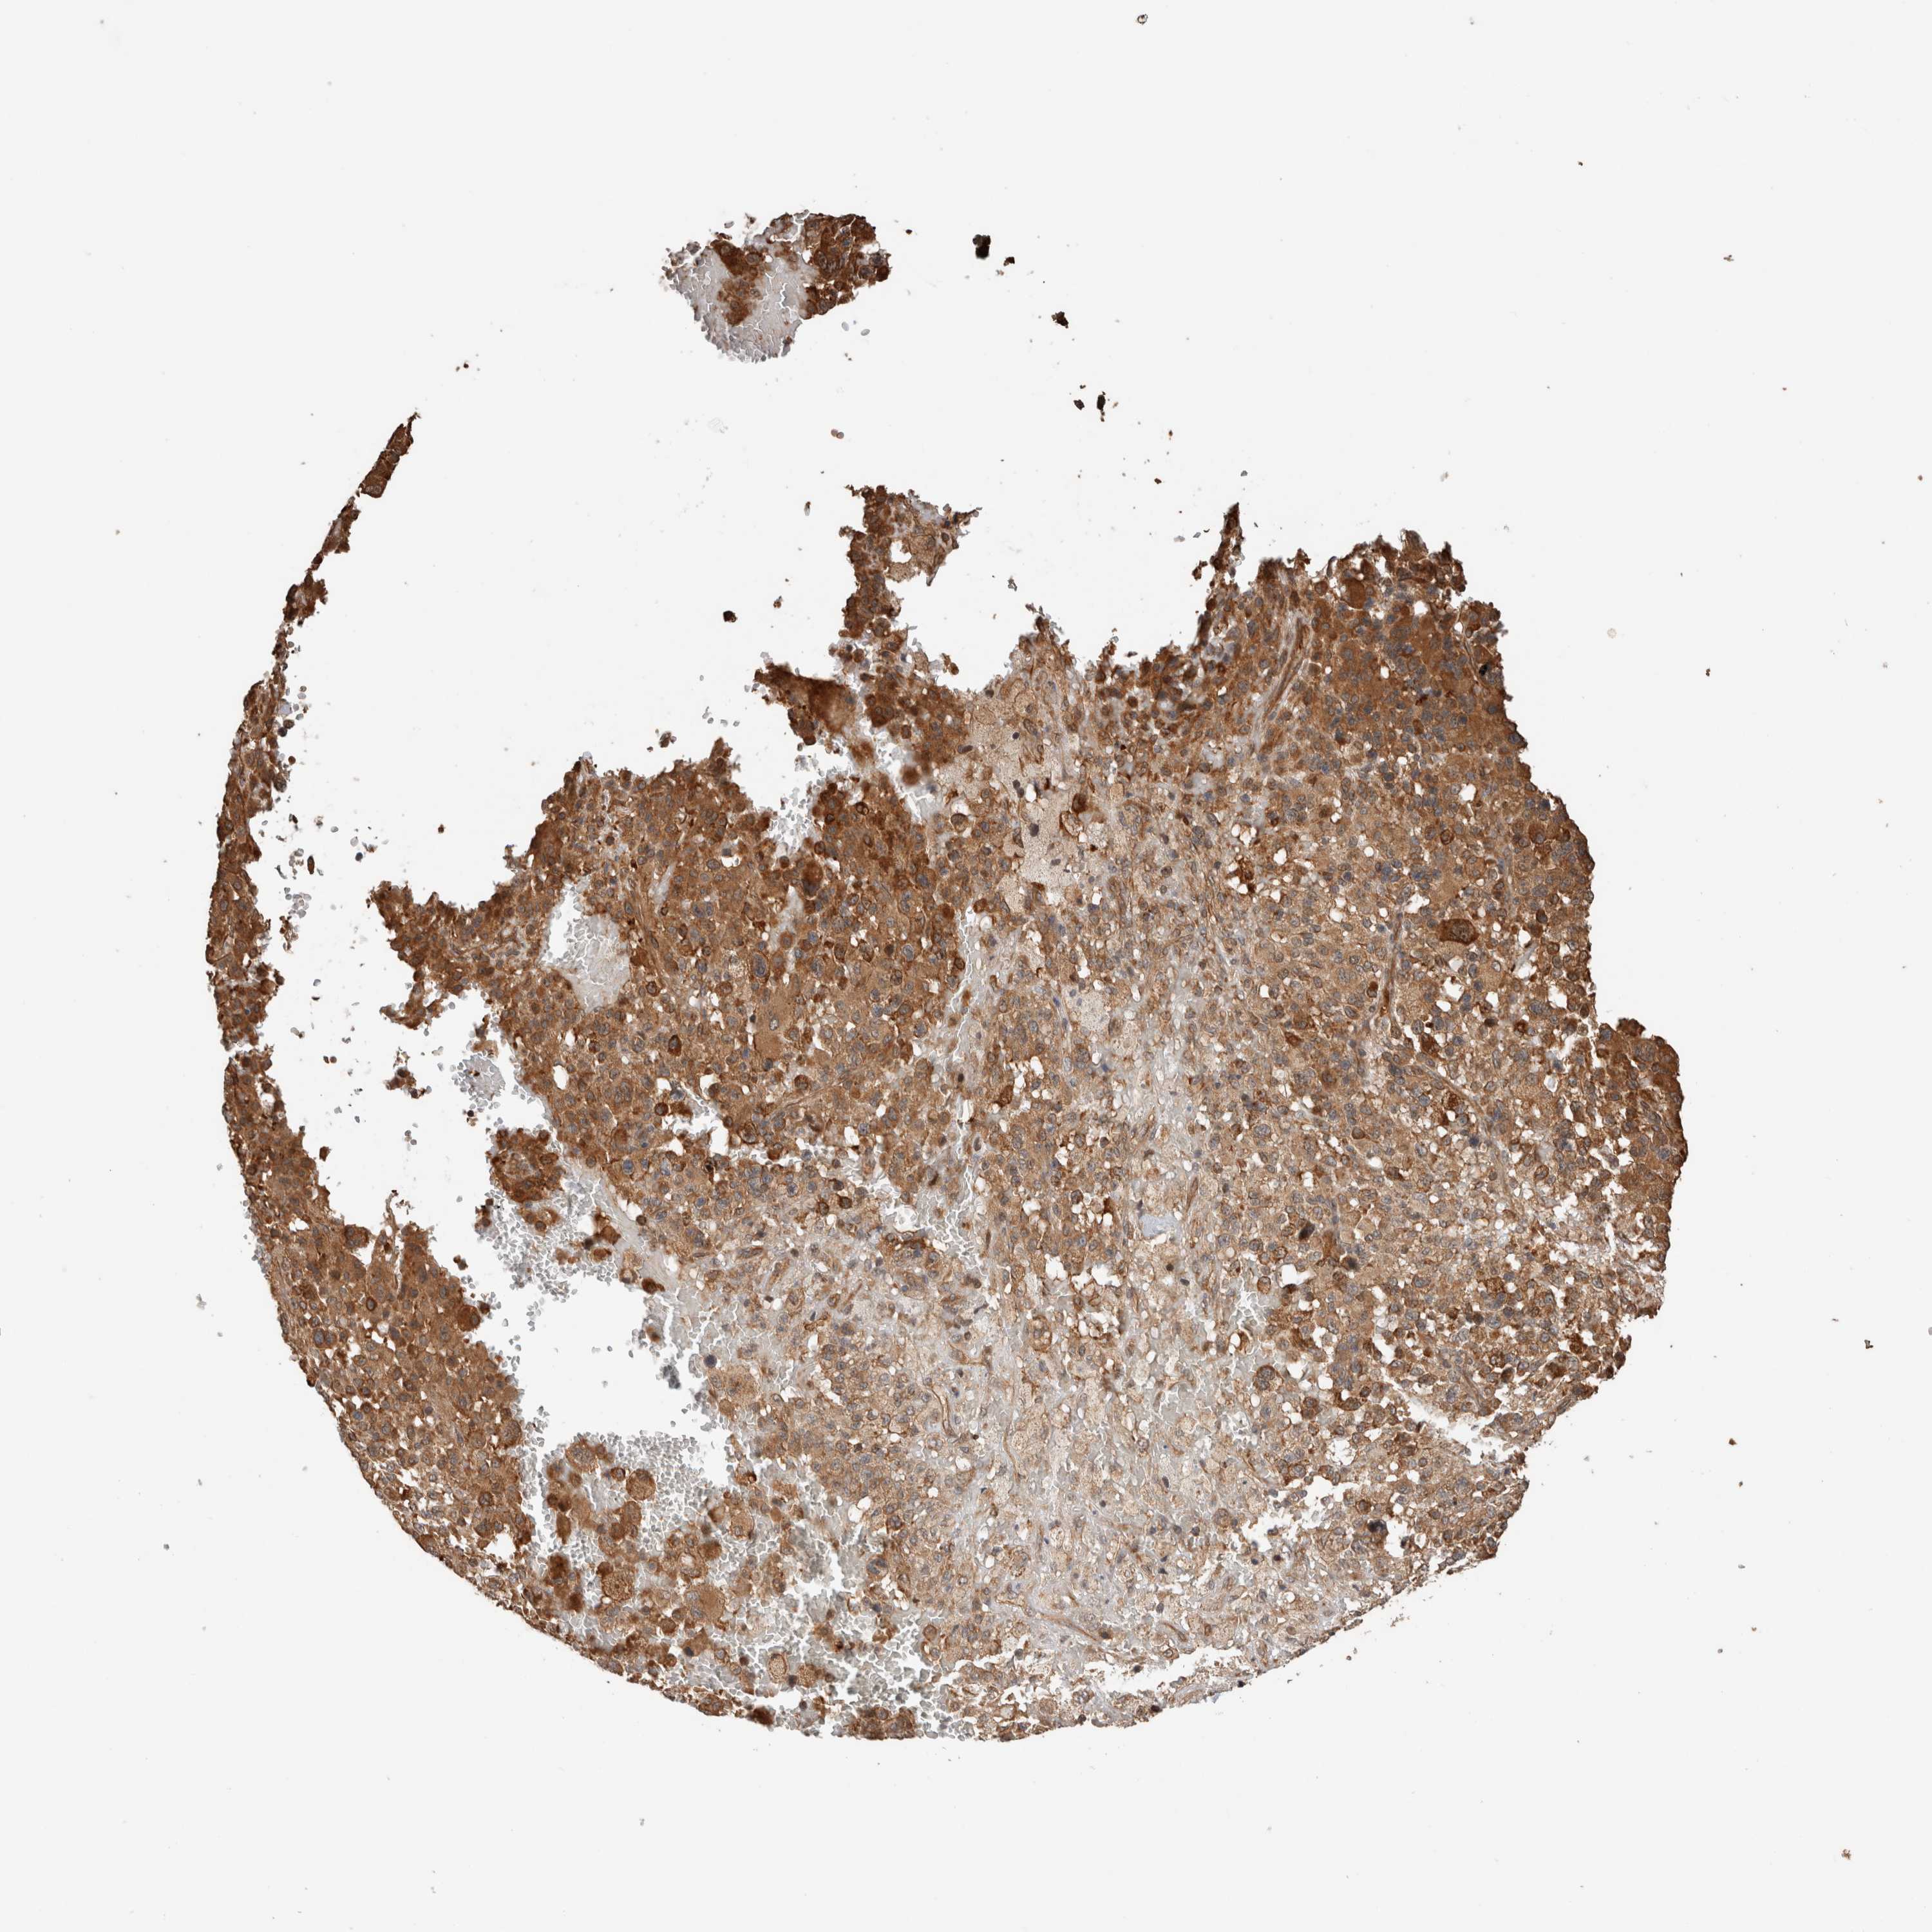

MELANOMA - Protein expressioni

A mouse-over function shows sample information and annotation data. Click on an image to view it in a full screen mode. Samples can be filtered based on level of antibody staining by selecting one or several of the following categories: high, medium, low and not detected. The assay and annotation is described here.

Note that samples used for immunohistochemistry by the Human Protein Atlas do not correspond to samples in the TCGA dataset.

Antibody stainingi

Antibody staining in the annotated cell types in the current human tissue is reported as not detected, low, medium, or high, based on conventional immunohistochemistry profiling in selected tissues. This score is based on the combination of the staining intensity and fraction of stained cells.

Each image is clickable and will lead to virtual microscopy that enables deeper exploration of all samples and also displays staining intensity scores, fraction scores and subcellular localization as well as patient and tissue information for each sample.

Antibody HPA024046

Antibody HPA024503

Antibody HPA024772

Staining

High

Medium

Low

Not detected

Intensity

Strong

Moderate

Weak

Negative

Quantity

>75%

75%-25%

<25%

None

Location

Nuclear

Cytoplasmic/membranous

Cytoplasmic/membranous,nuclear

Malignant melanoma, NOS

Malignant melanoma, Metastatic site